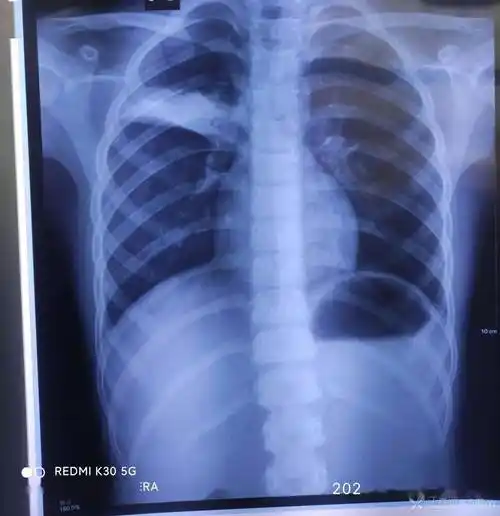

双胞胎反复肺炎的原因,及下一步处理. [病例帖]